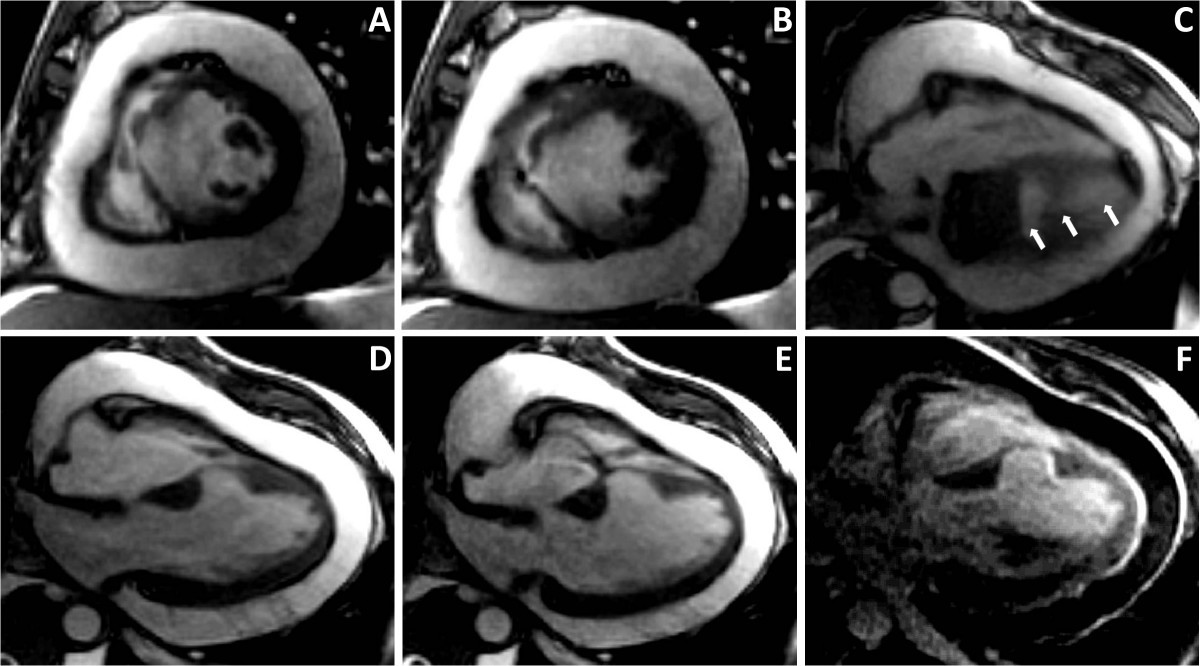

Get Chest Cardiac Contusion US. Cardiac contusion is an infrequent but occasionally serious complication of deceleration injury. We review our experience of cardiac contusion after blunt chest trauma, and we describe two very severe cases that manifested as cardiogenic shock.

Blunt cardiac injury (bci) encompasses a spectrum of pathology ranging from clinically silent, transient arrhythmias to deadly cardiac wall rupture.

While this patient's initial trauma may. Associated injuries include sternal fractures, rib fractures, and pulmonary contusion. Range is due to lack of standardized diagnostic criteria. Cardiac contusion is an infrequent but occasionally serious complication of deceleration injury.